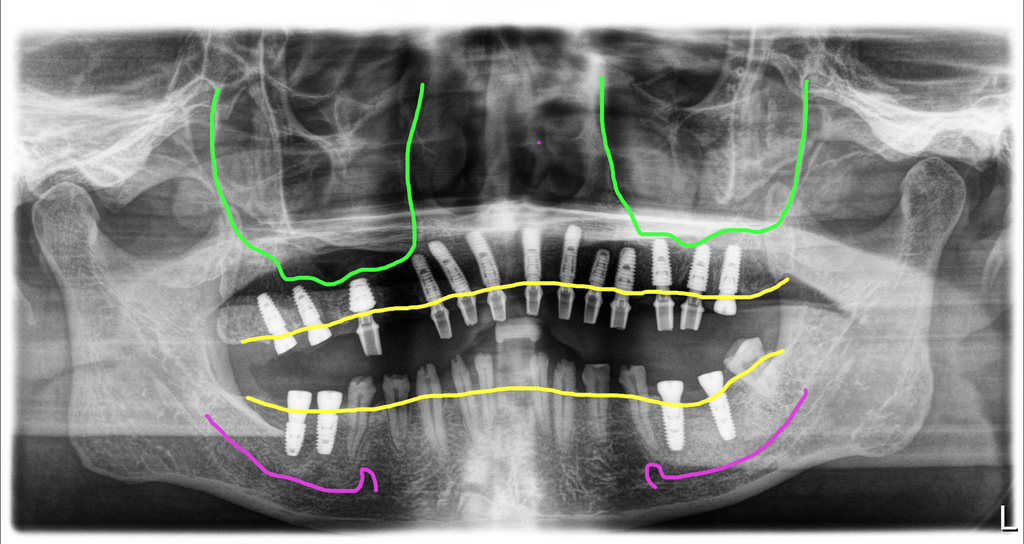

마무리 치료는 수술 후 4개월 이후에 가능한 상태였지만 미국에 계신 관계로 10개월 후에 방문하게 되셨어요.

모든 임플란트는 골융합이 잘 되었고 스캔바디를 끼우고 스캔을 한 다음 디자인해서 치아를 만들었습니다. 저희 병원은 치기공 100% 모두 자체적으로 가공을 하고 있어요. 모든 장비를 다 갖추고 있구요. 기공을 제가 직접 하게 된 스토리는 길어서 다른 글에서 보시면 될 거 같아요. 아무래도 제가 임상에서 깨달은 부분을 디자인에 직접 적용하기 위함이 큽니다.

스캔바디를 끼운 모습이구요.